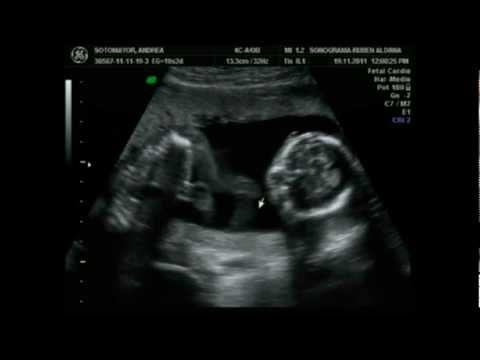

En la semana 17 de embarazo el bebé mide uno 13 centímetros de la cabeza a las nalgas y su peso de casi 200 gramos se realizaran. Semana 17 de Embarazo Ecografia. Desarrollo fetal en la semana 17 de gestación foto.

Semana 17 de Embarazo Ecografia. La exploración por ultrasonido en esta etapa le permite averiguar cómo se está desarrollando el bebé establecer si tiene defectos de desarrollo y evaluar marcadores específicos de posibles patologías. El cartílago gomoso de tu bebé se está convirtiendo ahora en hueso y al bebé ya le está creciendo algo de carne en sus huesos incluso ya tiene algo de grasa. A tu feto de 17 semanas le está creciendo un cordón umbilical más fuerte y. Esta semana 17 de embarazo tu pequeño está empezando a subir de peso. - había dolores en el abdomen secreción que normalmente no debería ser. Jason Levy MD Northside Radiology Associates Atlanta GA. Un Barriga de embarazada será cada vez más evidente generalmente unas pocas pulgadas debajo del ombligo. En esta etapa si el embarazo continúa un médico no lo derivará a un ultrasonido sin indicaciones especiales.

El sistema inmune de su bebé comienza a funcionar en esta etapa el cuerpo comienza a producir su inmunoglobulina e interferón. El Feto En La Decimoséptima Semana Del Embarazo. Cuál es el tamaño del vientre en esta etapa. En la semana 17 de embarazo el bebé mide uno 13 centímetros de la cabeza a las nalgas y su peso de casi 200 gramos se realizaran. Este es un período tranquilo y medido en el que la madre se siente bien. La toxicosis si lo fue casi terminó y la barriga aún es pequeña y no le da a la mujer ninguna sensación desagradable no se. Tu bebé a las 17 semanas de embarazo.